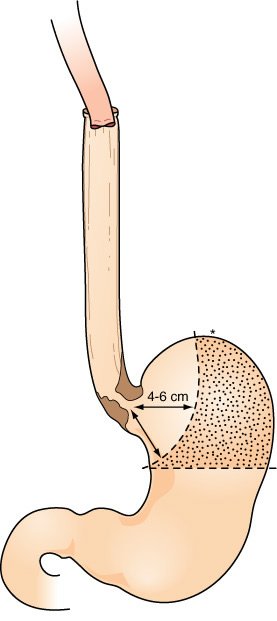

Esofagectomia torácica total e gastrectomia parcial proximal realizada para adenocarcinoma limitado à junção gastroesofágica e estômago adjacente. Tais tumores podem ser ressecados com uma margem gástrica de 4 a 6 cm, portanto, conservando totalmente a grande curvatura do fundo gástrico e aquele ponto (asterisco) que alcança a porção mais cefálica do pescoço. Uma hemigastrectomia proximal para tal tumor desperdiça esse segmento importante de estômago (área pontilhada) que pode ser utilizada para a reposição esofágica e contribui pouco em uma "operação para câncer".

Para tumores do terço distai do esôfago localizados na cárdia, a pequena curvatura proximal do estômago é ressecada até 4 a 6 cm distai à borda inferior macroscópica do tumor, preservando o ponto da grande curvatura que alcança cranialmente a anastomose com o esôfago cervical. Mesmo carcinomas esofágicos relativamente grandes podem ser ressecados através do hiato ampliado.